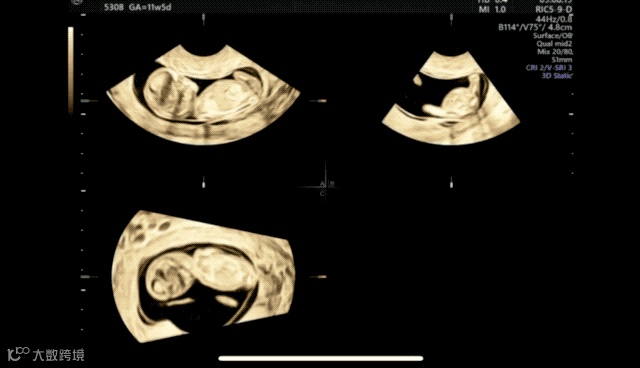

在超声机菜单上选取muti-plane、四幅画面,获得这张图。muti-plane多平面模式不同于render渲染模式,渲染模式下选择单幅画面只会显示3维图像,多平面模式就可以单独放大abc平面。

A平面是胎儿矢状切面,B平面是胎儿横切面,c平面是胎儿冠状切面。单纯旋转a切面很难获取标准正中矢状切面的,我们需要借助bc平面,只要bc平面标准了,a平面也自然是标准了。所以bc平面要选择能够快速识别是否标准的标志物,这里我选择了大脑镰,目标是b平面上大脑镰绝对垂直、c平面上大脑镰绝对平行,这样我们的a平面就是胎儿正中矢状切面了